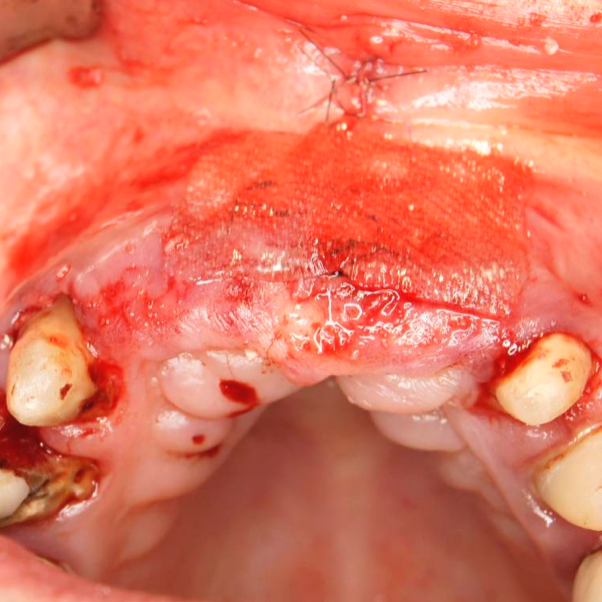

Während oder nach oralen Operationen, von der Extraktion von Zähnen bis hin zu rekonstruktiven Eingriffen, oder Implantationen, bietet BloodSTOP® iX eine schnelle und vorübergehende Kontrolle von Oberflächenblutungen.

BloodSTOP® iX absorbiert schnell Blut und verwandelt sich in ein klares Gel, um die Wunde mit einer transparenten Schutzschicht zu versiegeln, Blutplättchen zu binden und zu aktivieren, sowie die Gerinnung und Wundheilung zu unterstützen.

- Schließen des Osteotomiefensters zum Sinuslift

- Wundversorgung nach Entnahme von Weichgewebstransplantaten

- Sicherung der Schneider-Membran, auch als Perforationsversorgung

- Parodontale und chirurgische Wunden